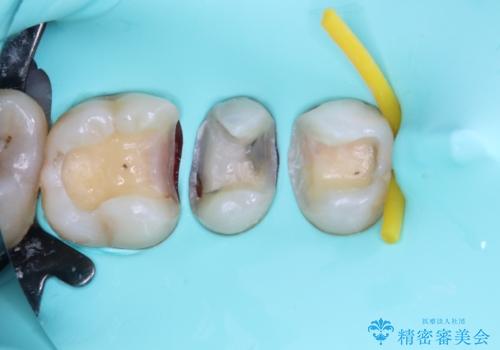

その他は銀歯のインレー(部分的な詰め物)が装着されており、それらはむし歯を除去した後にセラミックインレーにて修復治療を行い、左下と根管治療を行う左上の奥歯はオールセラミッククラウンにて補綴治療を行うこととしました。

根管治療の途中で、矯正治療の後戻りが気になるとのことで、下顎前歯の叢生を改善するためにマウスピース矯正を並行して行いました。